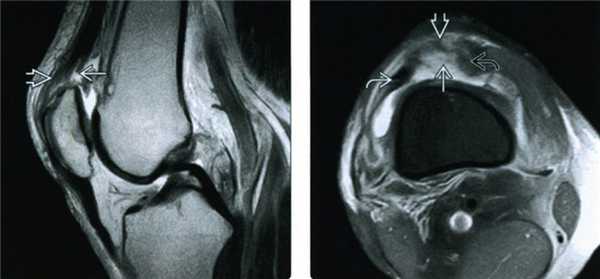

МРТ. Этот метод исследования позволяет визуализировать мягкие ткани в области коленного сустава, в т.ч. и сухожилие четырехглавой мышцы. МРТ позволяет оценить степень и локализацию разрыва. Иногда МРТ назначается для исключения других состояний, проявляющихся похожими симптомами.